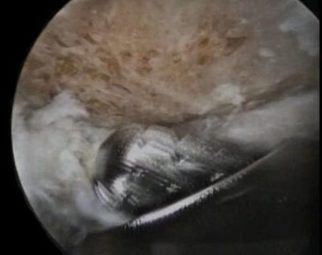

Foto 1 y 2, se observa durante la artroscopía el fresado del acromión